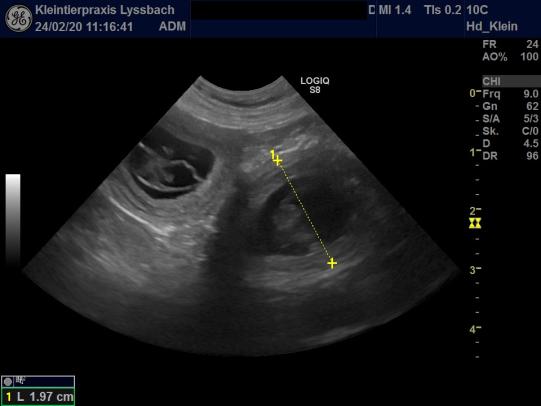

Rund drei Wochen nach dem Decken führen wir bei Duna einen Trächtigkeitsultraschall durch und können erfreut feststellen, dass die Hündin mit mindestens 6 Welpen trächtig ist - die Fruchtblasen sind in der Zwischenzeit schon ca. 2 cm gross und der Herzschlag ist sichtbar.